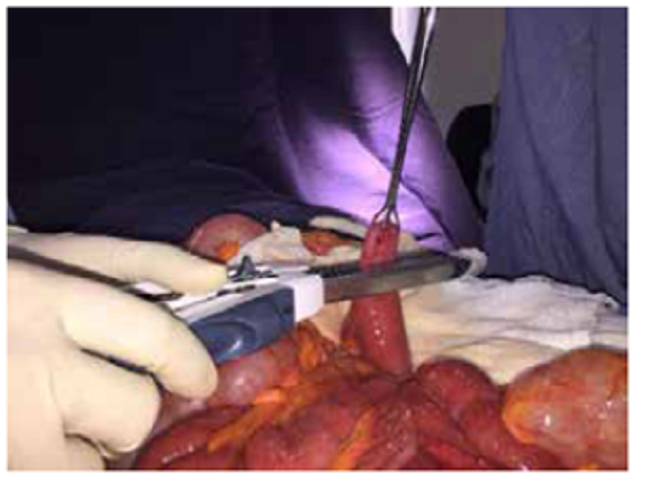

Se hospitalizó para observación y, 48 horas después presentó signos de irritación peritoneal más distensión abdominal importante, por lo que se sometió a laparotomía. En el yeyuno proximal, se encontró una zona de transición por vólvulo del asa intestinal con giro sobre su eje longitudinal, y dilatación proximal y distal de las asas intestinales delgadas. A 10 cm de ángulo de Treitz, se encontró un divertículo en yeyuno, sin serosa, comprometido por el vólvulo e hipoperfusión asociada (figura 3). Con estos hallazgos, se decidió practicar una resección intestinal con anastomosis yeyuno-yeyuno mediante sutura lineal mecánica (figuras 4 y 5).